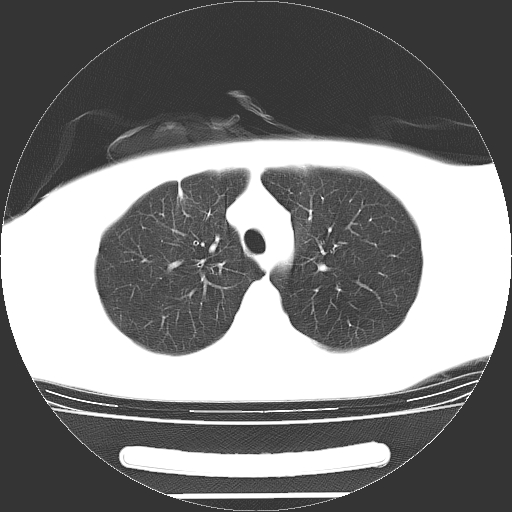

标题: CT19767:男,20岁,右侧气胸行闭式引流术后五天CT检查。 [打印本页]

男,20岁,右侧气胸行闭式引流术后五天ct检查看肺内是否有肺大泡,纵隔窗未见异常,未上传。

1)右侧胸腔闭式引流术后导管留置。2)右肺未见肺大泡。

未见肺大泡,还有微量气体。